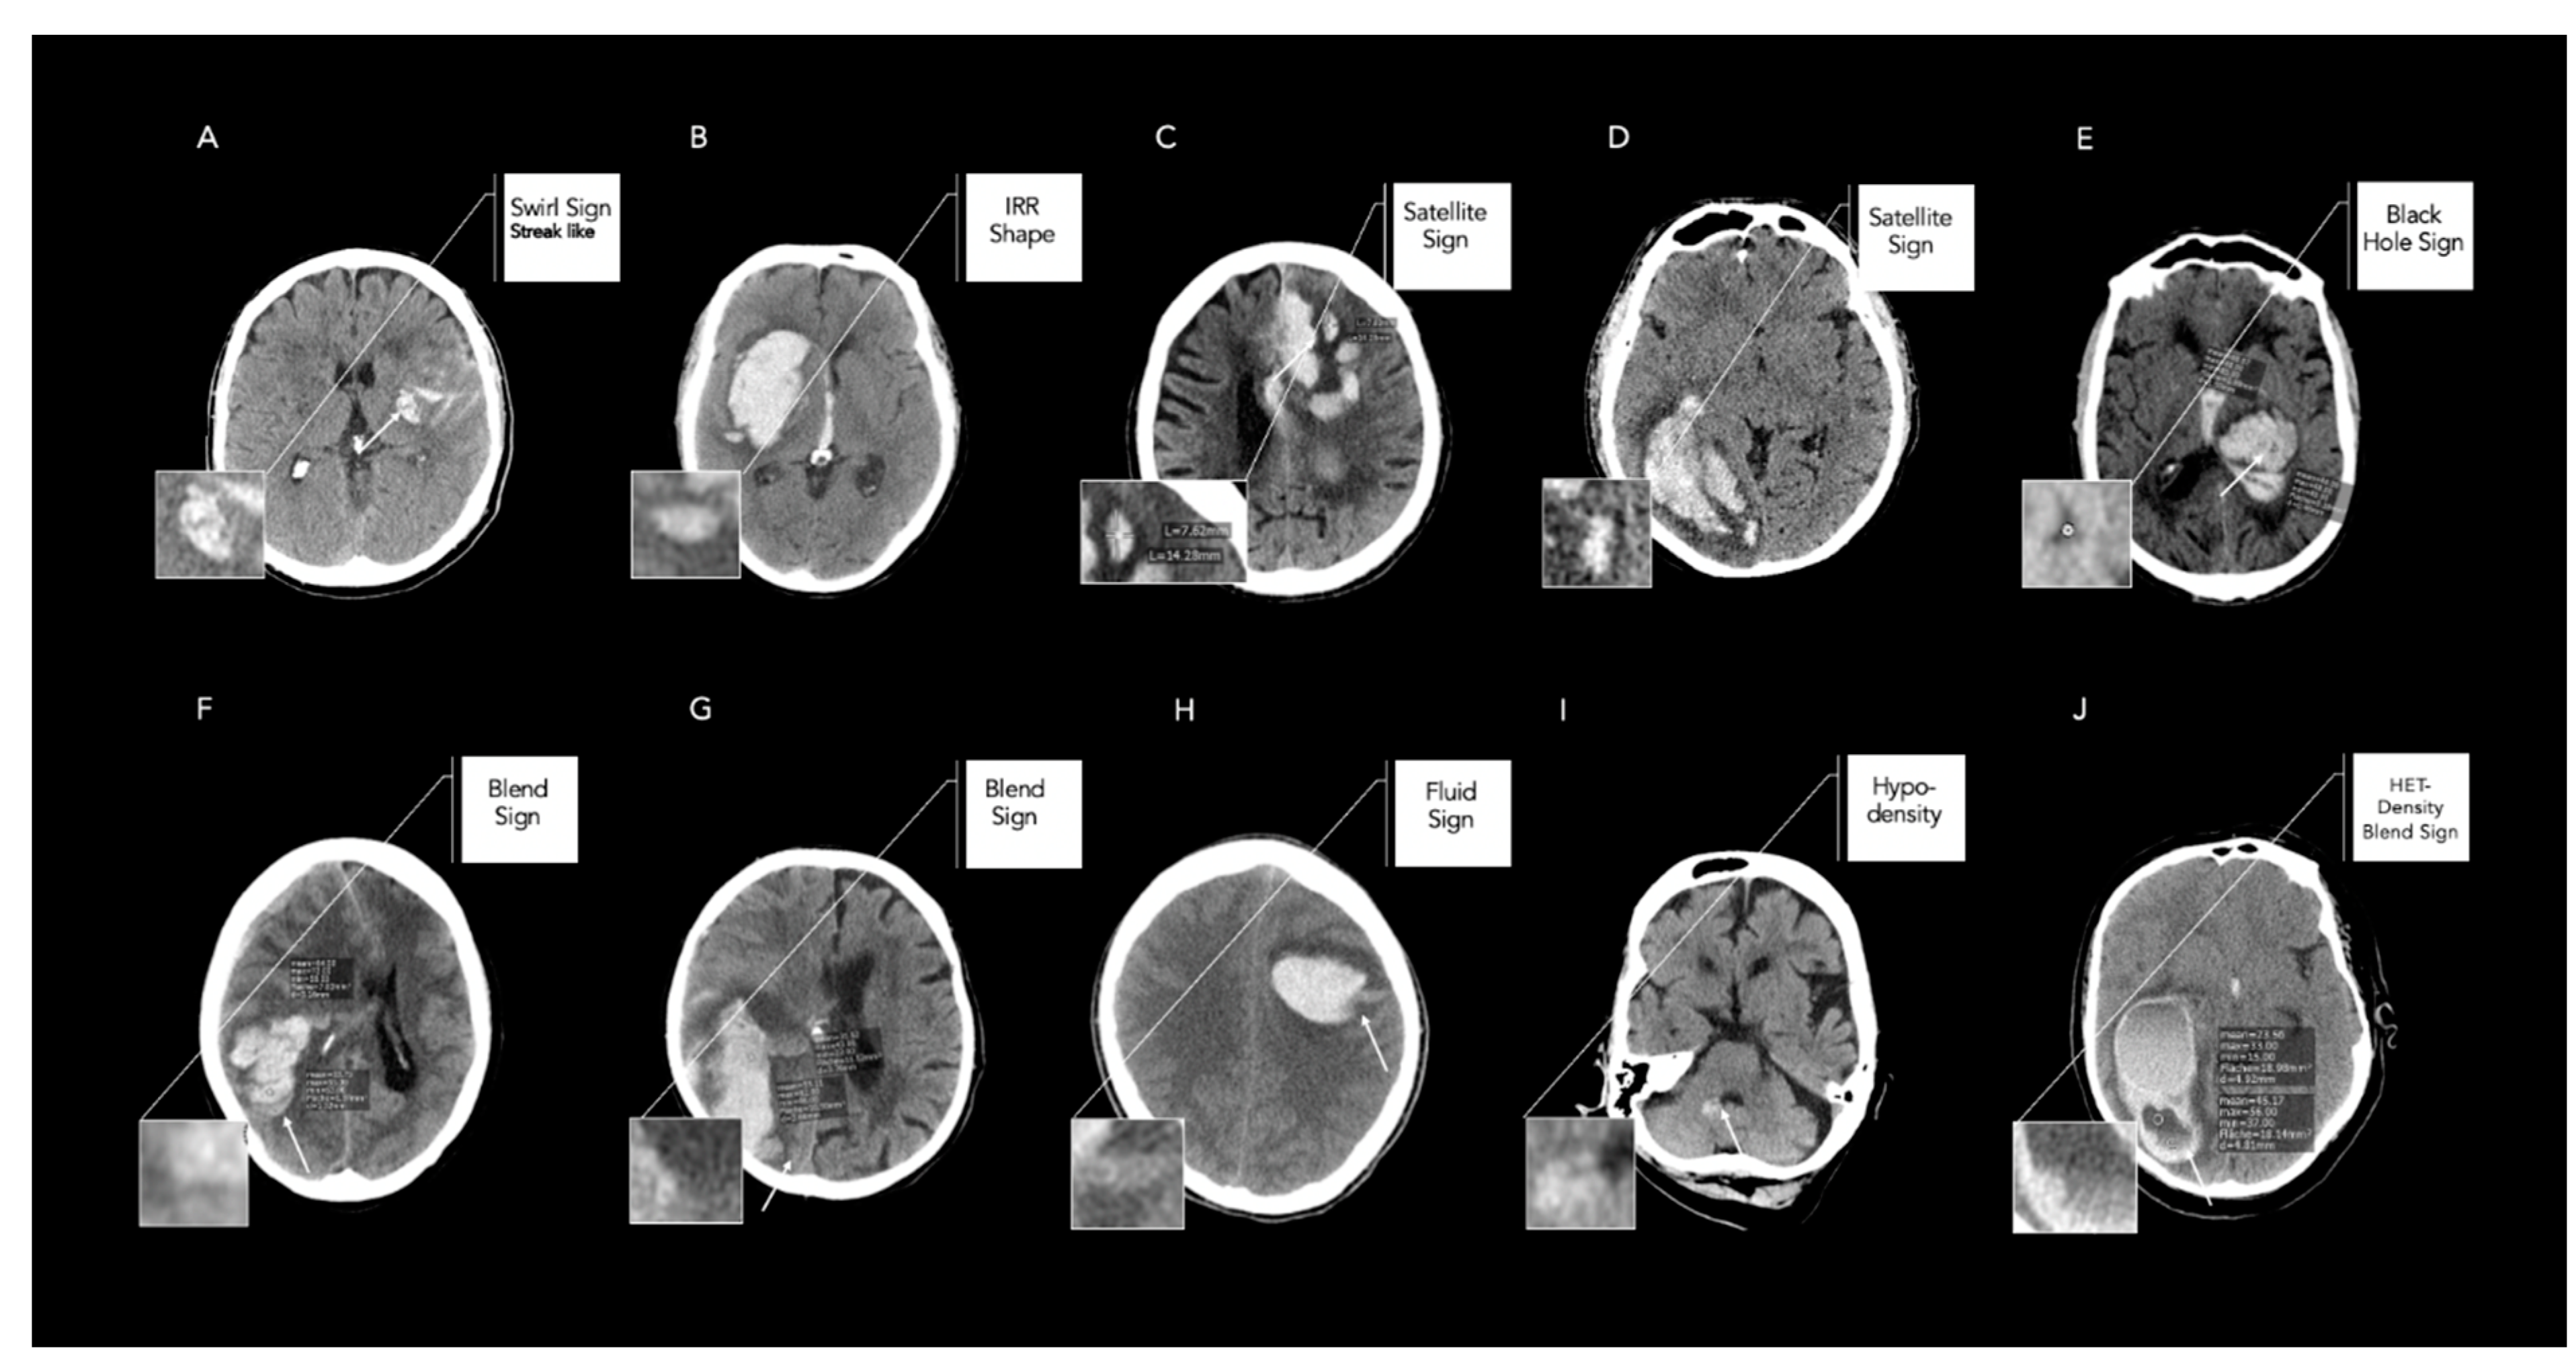

Figure 1.

Illustrative examples of false-positive and -negative rated Noncontrast Computed Tomography (NCCT) markers between different raters. Legend: Illustrative examples of interpretation of Noncontrast Computed Tomography markers with maximal discordances between one radiology resident, one radiology fellow, and one neuroradiology fellow. (A) Streak-like swirl sign was rated false negative by the resident. (B) IRR shape rated false negative as Barras II versus qualifying as Barras III by the neuroradiology fellow. (C) Satellite sign rated false negative, with a diameter greater than 10 mm, as shown by the neuroradiology fellow’s measurements. (D) Satellite sign rated false positive, as the small hematoma shows signs of connection with the main hematoma according to the fellow. (E) Black-hole sign rated false positive, with encapsulated hypodensity but density differences less than 28 HU, as shown by the neuroradiology fellow’s measurements. (F,G) Blend sign rated false positive, with well-defined margins of density changes within the hematoma but density differences less than 18 HU, as indicated by the neuroradiology fellow’s measurements. (H) Fluid sign rated false positive with a discrete straight line above the hyperattenuating area which is not clearly separated by a hypoattenuating area of hemorrhage or edema. (I) hypodensity rated false positive as no strict encapsulation was defined by the neuroradiology fellow. (J) HET density rated correctly by two raters. Fluid sign was rated by neuroradiology fellow. In contrast, blend sign was rated false positive, with density measurements less than 18 HU, by the resident.

In this study, we aimed to determine the link between the level of experience in raters and the reliability of the assessment of NCCT markers. Our previous results demonstrated good-to-excellent levels of inter- and intrarater reliability and contribute to the results presented by Dowlatshahi et al. [6,7]. However, the different levels of experience amongst raters with a radiological background may result in significant interobserver variability and differences in the diagnostic accuracy for predicting acute HE. Therefore, the results of our analysis highlight several novel important findings. Firstly, the reliability of NCCT markers varied among raters with different levels of experience. Nevertheless, eight out of nine NCCT markers showed substantial-to-almost-perfect agreement, whereas a moderate agreement was only found for the swirl sign. The illustrative examples shown in Figure 1 demonstrate that especially very nuanced density changes, such as the streak-like morphology of the swirl sign (Figure 1A) or scattered, primarily satellite-suggestive hematoma with yet subtle connections to the main hematoma (Figure 1D), were difficult to identify. Moreover, the strict encapsulation of the hypodense area within the hematoma (hypodensities) was false positively rated, especially in cases of small hematomas with very nuanced NCCT feature attributes, as shown in Figure 1I. Semiquantitative measurements were error-prone for calculating the correct diameter of the hemorrhage for assessing the satellite sign (Figure 1C,D) and density differences for the black hole sign or blend sign (Figure 1E–G). In line with this, raters from different clinical backgrounds also tended to obtain higher proportions of positive ratings of NCCT markers according to a recently published study [27]. Variabilities in the ratings of the IRR shape, heterogenous density, and island sign may be further influenced by differences in the slice position of the region of interest (ROI), which should be placed on the axial slice with the largest cross-sectional area of the hematoma (Figure 1B,J) [5]. This is of clinical importance, as measurement error may potentially obscure the true predictive effects. Evaluated AUC differences for acute HE prediction were minor and found in only two out of nine NCCT markers. Our study had some limitations. Firstly, our study offered only limited conclusions to whether variances of agreements were attributed to the level of experience, as this would require a larger sample size within each category of experience included. Furthermore, given that the imaging analysis in an emergency setting is often much more rushed than in an elective case, accounting for the reading time may have resulted in additional variability of the readings. Secondly, our findings were derived from a retrospective analysis and require prospective confirmation. Finally, the imaging protocol was not standardized across participating sites. Nevertheless, there is no evidence that the NCCT acquisition technique influences NCCT markers’ detection [5].